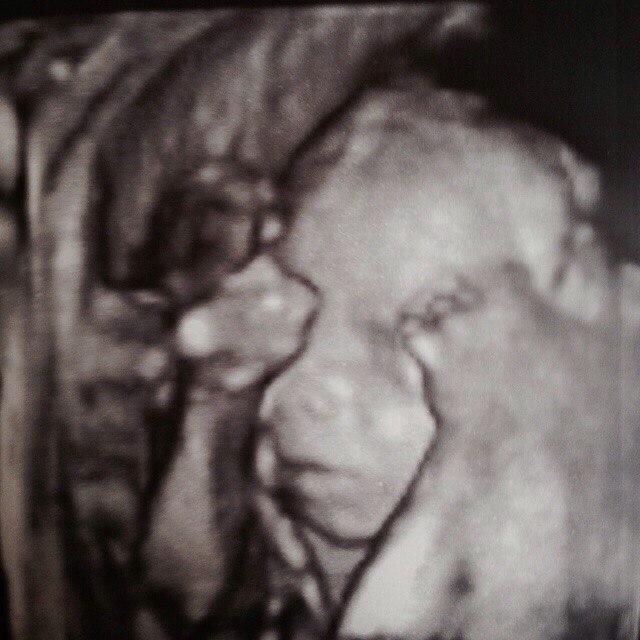

волновалась перед узи!))Мальчишка наш закрылся ручками и не хотел открывать личико, а потом и ножку к лицу подтянул))))Зевал лежал и даже погладил себя по головке...По показаним все хорошо (ттт). 330 гр))

фух, камень с души)) И да, я наеонец-то начала чувствовать пиночки!